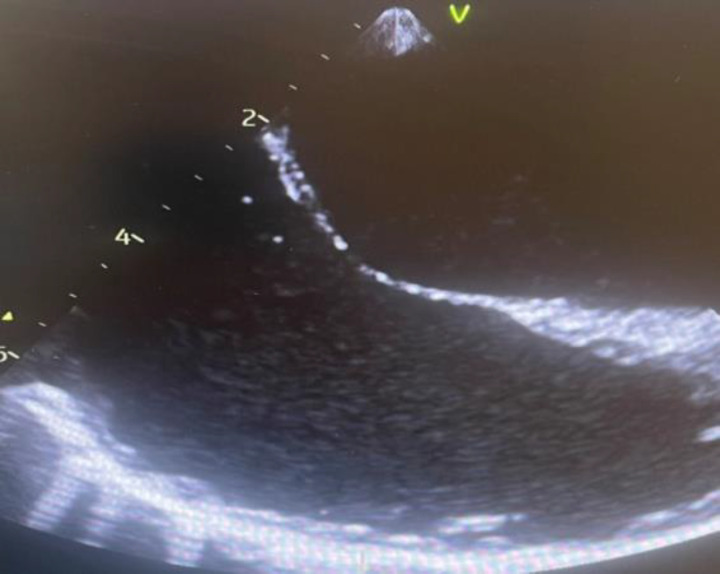

Case presentation: A 45-year-old male patient was admitted into the surgical intensive care unit with Fournier's gangrene, septic shock, and acute kidney injury (AKI). The patient was managed by invasive ventilation, noradrenaline, vasopressin, and renal replacement therapy. He developed Escherichia coli bacteremia and candidemia. We added meropenem and antifungal to the therapy. The transthoracic echocardiography showed EV vegetation and thread-like vegetation in the right coronary sinus, which was confirmed with transesophageal echocardiography. With aggressive therapies, the patient recovered from septic shock, organ dysfunction and was successfully liberated from invasive ventilation. The patient was discharged home on day 27. The antibiotics and antifungal were continued for 6 weeks. Two weeks after discharge, the follow-up echocardiogram was normal, and he was doing well.